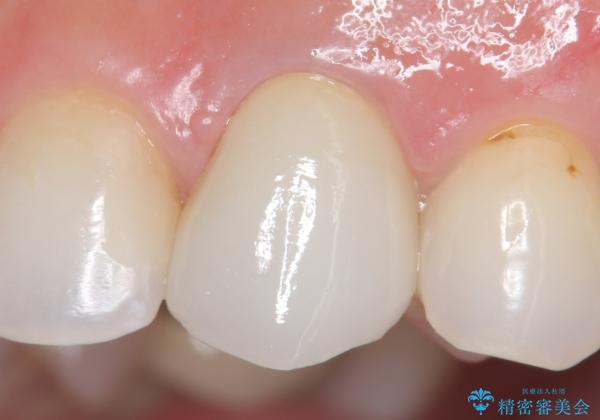

再根管治療後、オールセラミッククラウン(スペシャル)による補綴を行いました。

前歯の補綴ではオールセラミッククラウンを希望される患者様が多いですが、オールセラミッククラウンの中でも、エコノミー、スタンダード、スペシャル、エクセレントとランクがあります。

その中でも特に審美性が高いのがスペシャル、エクセレントです。スペシャル、エクセレントは口腔内写真をもとに熟練の技工士が、患者様の口腔内に合わせたオーダーメイドのクラウンを製作致します。